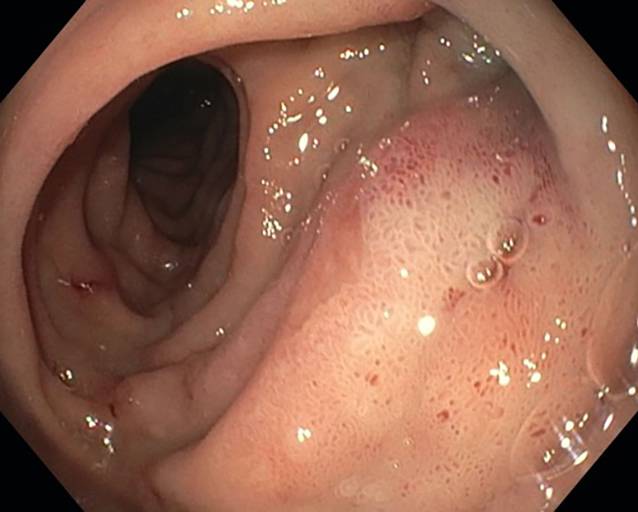

The dOFD has a diameter of only 6 mm. Transnasal insertion was performed under endoscopic view using the same technique as with a gastroduodenal drainage tube. The intestinal feeding section of the dOFD was endoscopically advanced along the pylorus into the duodenum, and the dOFD was further advanced and placed deep into the duodenum with the open-pore film segment covering the defect region (Fig. 3).

Fig. 3

Placement maneuver for the double-lumen open-pore film drain. Feeding tube (iT), transition to the film-wrapped segment (DE), sutured perforation defect (P) of the nephrostomy catheter with perifocal edema and local signs of inflammation